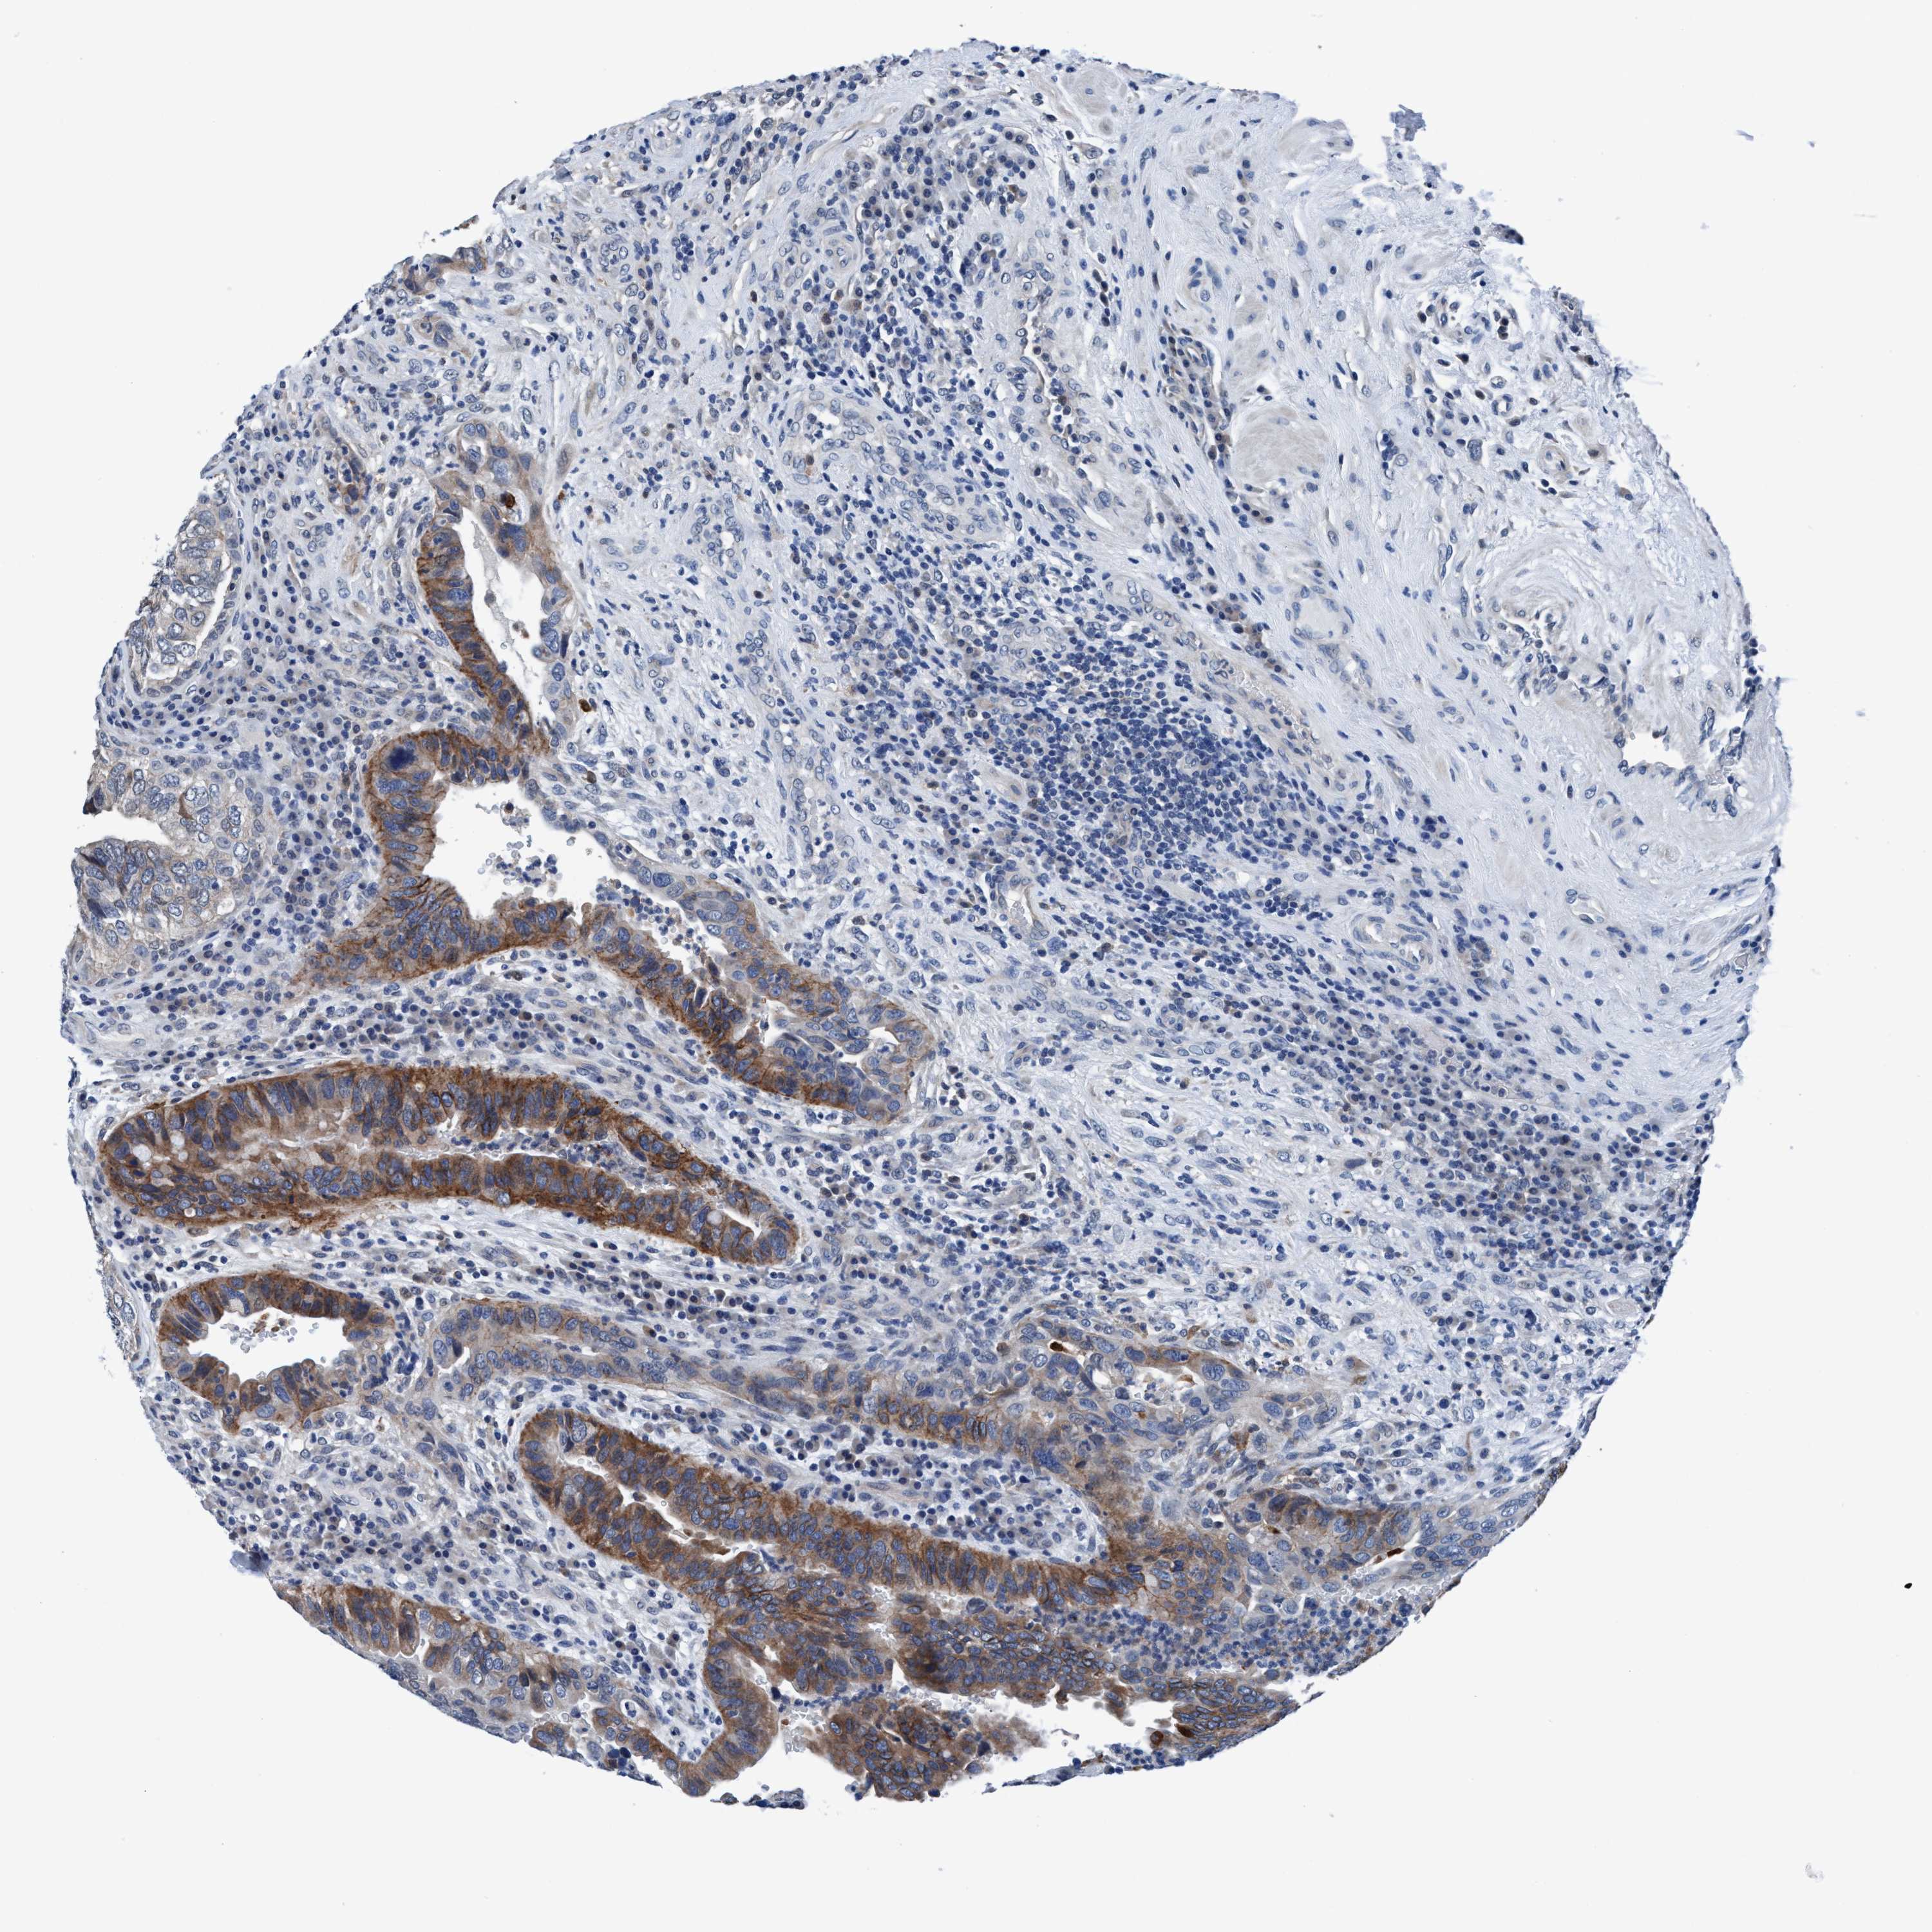

UROTHELIAL CANCER - Protein expressioni

A mouse-over function shows sample information and annotation data. Click on an image to view it in a full screen mode. Samples can be filtered based on level of antibody staining by selecting one or several of the following categories: high, medium, low and not detected. The assay and annotation is described here.

Note that samples used for immunohistochemistry by the Human Protein Atlas do not correspond to samples in the TCGA dataset.

Antibody stainingi

Antibody staining in the annotated cell types in the current human tissue is reported as not detected, low, medium, or high, based on conventional immunohistochemistry profiling in selected tissues. This score is based on the combination of the staining intensity and fraction of stained cells.

Each image is clickable and will lead to virtual microscopy that enables deeper exploration of all samples and also displays staining intensity scores, fraction scores and subcellular localization as well as patient and tissue information for each sample.

Antibody HPA008423

Urothelial carcinoma, Low grade

Urothelial carcinoma, High grade